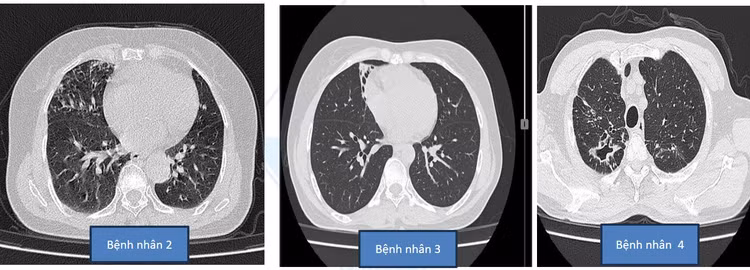

Bệnh phổi NTM thường khó chẩn đoán do tổn thương phổi tiến triển chậmBệnh phổi NTM thường khó chẩn đoán do tổn thương phổi tiến triển chậm

Bệnh thường khó chẩn đoán do tổn thương phổi tiến triển chậm (có thể mất 20 tháng bệnh nhân mới biểu hiện triệu chứng và trên hình ảnh học). Triệu chứng mạn tính dễ nhầm với bệnh lý khác của phổi như viêm phổi, giãn phế quản... nếu không được theo dõi định kỳ.